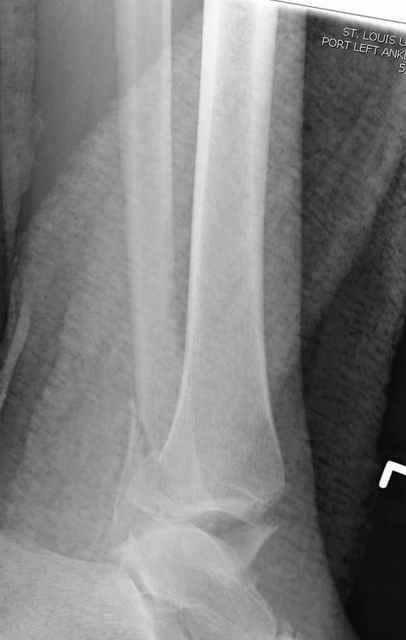

I agree with primary spanning ex-fix, but IMHO some days later it is worth to attempt to restore tibial articular surface as much as possible, using ligamentotaxis and joystick wires under image intensifier. Maybe even put autografts through limited incisions.

By the way many colleagues reported good experience with Norian SRS (i didn't have a chance to play with it yet)- maybe such the case is suitable for its application and it could be injected to fill some gaps?

A propos fibular fixation if one is eager to stabilize it separately. In the fracture pattern a way of closed fixation by V-shaped stressed wire (advanced by colleagues from Moscow, prof. Lazarev A.F. et al.) must be excellent. We use indirect closed reduction by the external fixator. Example attached, that fibular fracture is even more suitable for plating but the wire did the job.